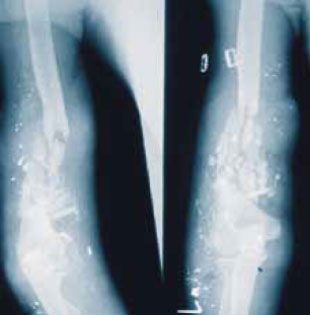

Полная диагностика может также включать рентгенографию, за исключением сквозных ранений мягких тканей, при которых такое исследование не требуется. Необходимо сделать по одному снимку участка тела выше и ниже входных и выходных ран. Деформация или фрагментация пули, которая на рентгеновских снимках хорошо видна как «свинцовый дождь», является надежным показателем тяжелого повреждения тканей (рисунок 1). Нужно отметить, что многие чужеродные материалы рентгеноконтрастны, например, кусочки обуви или одежды, грязь, листья и трава, пластиковые осколки некоторых мин. С другой стороны, бывает трудно различить ранящий снаряд на фоне нормальной анатомической рентгеноконтрастности некоторых анатомических органов. Тяжелый раздробленный перелом также ведет к обширному повреждению мягких тканей. Наличие рентгенографии помогает, но не является совершенно необходимым для диагностики переломов в зоне боевых действий.

Рисунок 1. «Свинцовый дождь». На рентгенограмме наблюдается тяжелый раздробленный перелом плечевой кости вследствие разрушения пули